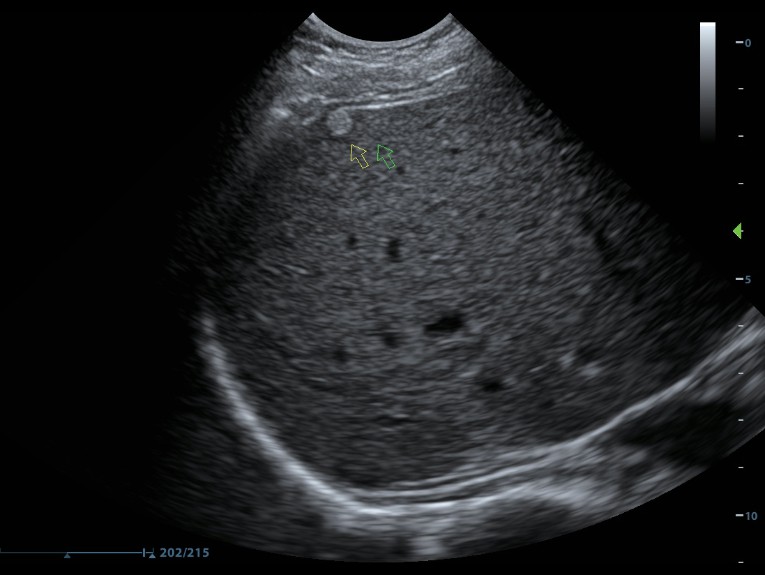

Клинические изображения